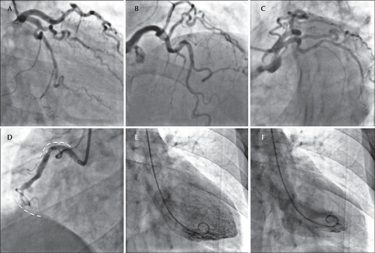

Как проводится ангиография?

- Ангио производится врачами, обученными в специально оборудованной лаборатории.

- Пациент должен быть спокоен во время процедуры. При необходимости для этого можно назначать транквилизаторы

- Пациент должен лежать на спине на столе для ангиографии.

- Подключается к аппаратам, которые показывают частоту сердечного ритма, кровяное давление и уровень кислорода в крови.

- Операция может быть в области паха или запястья. Область, в которой выполняется процесс, очищается и стерилизуется йодным антисептическим раствором.

- Пациента укрывают стерильными покрывалами.

- В область, в которую будет входить катетер, вводится локальный анестетик.

- В артерию в паху или запястье вводится специальная игла, и в месте входа помещается оболочка. Этот чехол называется ‘sheet’.

- Специальная мягкая тонкая труба, называемая катетером, через оболочку продвигается к основным артериям сердца. Это не причиняет боль и не ощущается больным.

- Через катетер контрастное вещество (краситель) транспортируется к сердцу.

- Изображения вен принимаются через рентгеновские лучи, в то время как сердце работает. Эти изображения сохраняются в цифровой среде. Отчет может быть отслежен врачами позже с целью написания.

- Коронарная ангиография проводится безболезненно. Как только область, в которой будет проведена операция, будет обезболена, игла не будет ощущаться.